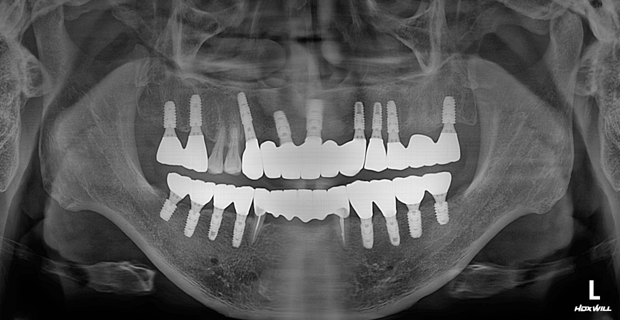

치료 전

치료 후

40대 남성 환자분으로, 전반적으로 치아들이 치주염에 이환되어 살릴 수 있는 치아가 거의 없었던 경우입니다.

전체 치아를 발치하지 않고 보존하여 쓸 수 있는 오른쪽 위 작은 어금니들과 아래쪽 송곳니들을 살려 전체 치아 치료를 해 드렸습니다.

수직고경도 회복하여 심미적으로도 우수하게 좋아졌습니다.